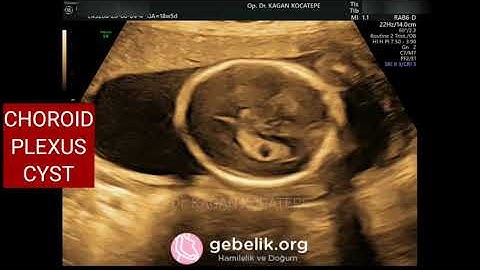

Ultrasound Bilateral Large Fetal Chroid Plexus Cyst | Associations